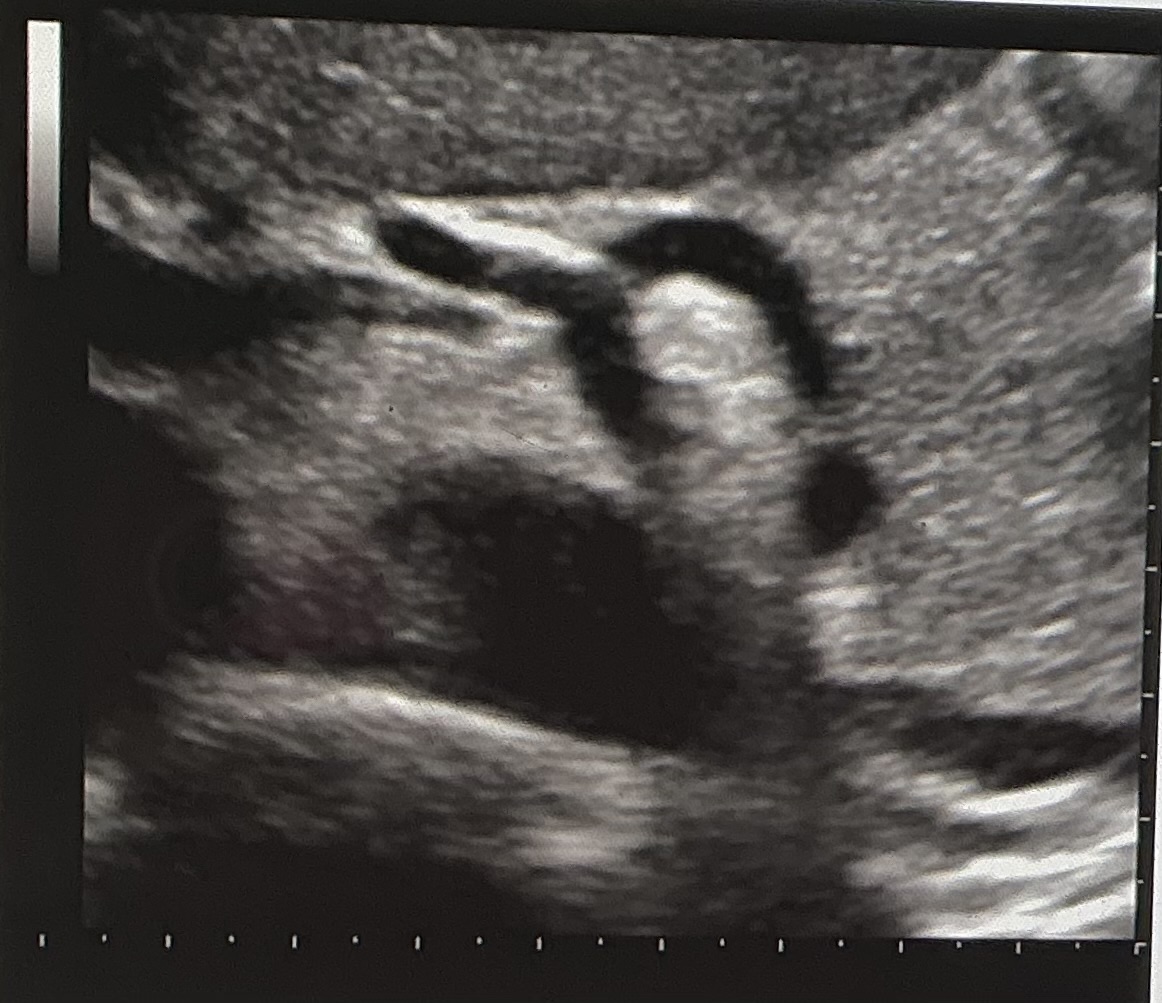

The sonographic image displayed is in which of the following orientations

transverse

What vascular structure is visualized?

celiac axis and branches

If you are scanning your patient in the transverse plane at the level demonstrated in the image, which way would you slide your transducer to see the SMA?

inferiorly